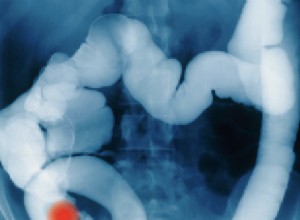

Dépistage du cancer colorectal en Flandre : test des selles tous les 2 ans pour 1,4 million de personnes